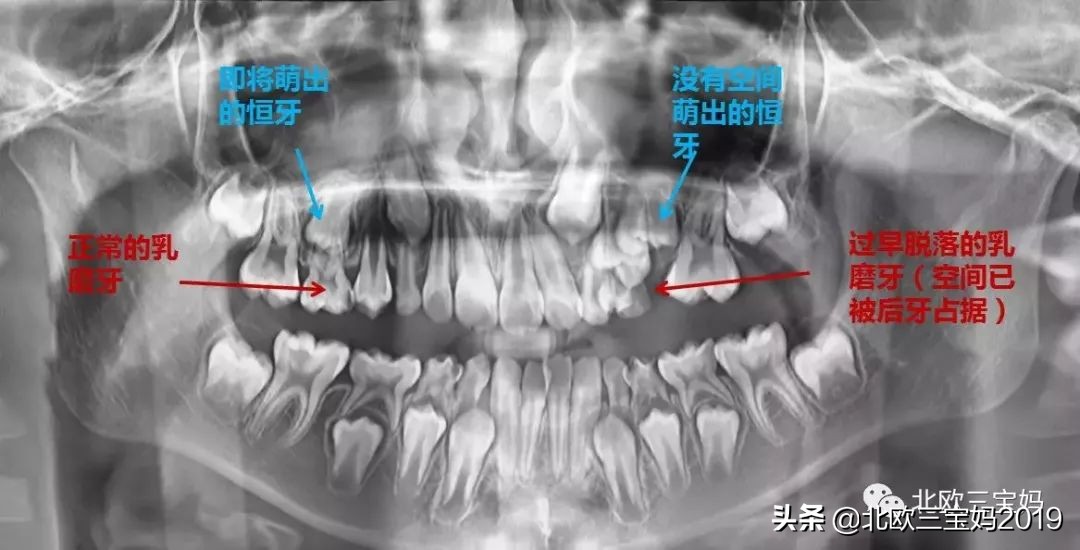

除此之外,乳牙被蛀缺失掉,空出来的位置势必要会被其他的牙挤占,导致这个位置上的恒牙没地方长出来,只能长歪

以下是乳牙期及替牙期常见的问题,很容易引发错颌畸形。

以后的恒牙被推挤得异位萌出,不在自己应该长得地方长出来,很容易变得东倒西歪、乱七八糟;